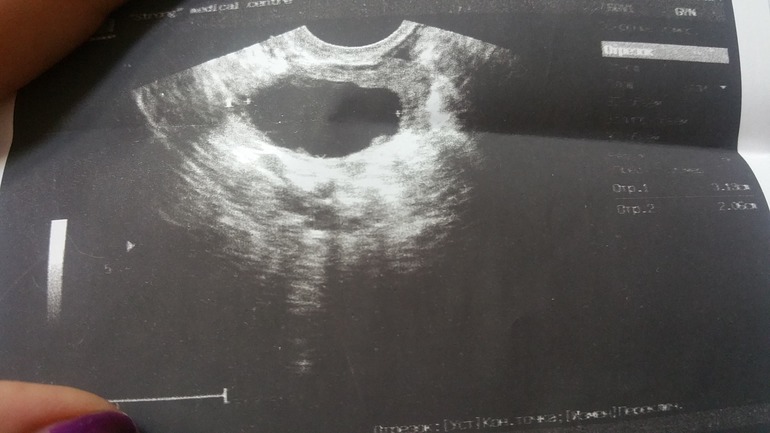

10дц

Врач сказала что овуляция уже случилась,размер 30×20мм.Вокруг фолликула жидкость, и так же В заднем своде жидкость высотой 15мм.И что фолликул разплылся,поэтому и такие размеры.Что скажите вы?это была овуляция? Или он сдулся?